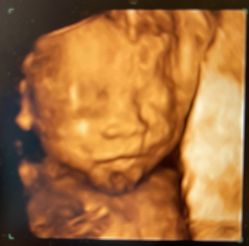

• -北京俪婴妇产医院(朝阳大悦城店)

相册

T9 上传于 22-07-02 | 报错